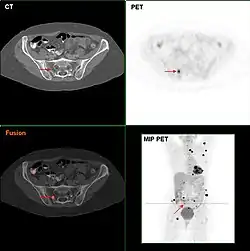

Wurde eine Krebserkrankung entdeckt, dann muss ihre Ausbreitung genau festgestellt werden, bevor über die beste Therapie beraten werden kann. Die Erkrankungsfälle werden in Stadien mit ähnlicher Therapie und Prognose eingeordnet. Die Leitlinien enthalten genaue Vorgaben für diese Stadienbestimmung (englisch staging). Sie basieren auf Anamnese und körperlicher Untersuchung, Blutuntersuchungen, und fast immer auf Schnittbildverfahren wie Computer- und Kernspintomographie sowie der (allerdings teuren) PET. Jede Tumorart bevorzugt bestimmte Ausbreitungswege, etwa bestimmte Lymphknoten, Leber oder Skelett, die gezielt abgesucht werden. Blutmesswerte sind etwa bei Leukämien oder dem multiplen Myelom wesentlich.